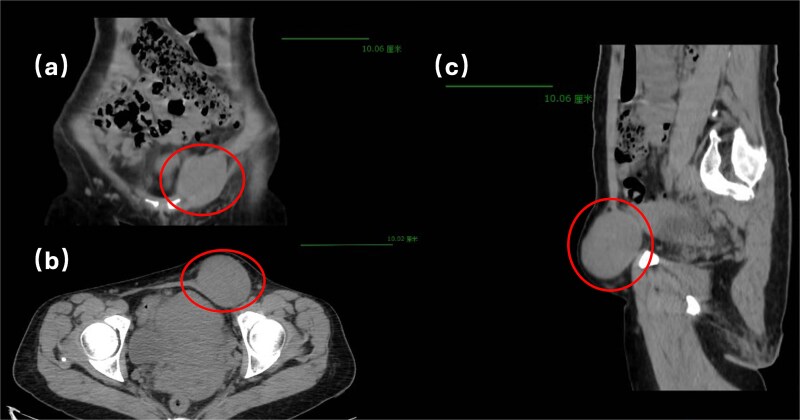

起源于子宫圆韧带的腺肌瘤是一种非常罕见的病理实体。考虑到圆形韧带穿过腹股沟管的解剖过程,这种结构的病理病变在临床上可能表现为盆腔或腹股沟肿块,因此需要从广泛的其他病理情况中进行区分。具有特殊临床意义的是,引起腹股沟疝的腺肌瘤相关表现非常罕见,最终的诊断确认取决于组织病理学证实。我们在此报告一例腹股沟管内原发性圆形韧带腺肌瘤,旨在提高临床认识,为同类临床情况的诊断和治疗决策提供循证指导和优化。

Adenomyoma originating from the round ligament of the uterus represents a remarkably uncommon pathological entity. Considering the anatomical course of the round ligament through the inguinal canal, pathological lesions in this structure may clinically present as pelvic or inguinal masses, thereby requiring differentiation from a broad spectrum of alternative pathological conditions. Of particular clinical significance, adenomyoma-associated manifestations causing inguinal hernia remain exceedingly rare, with definitive diagnostic confirmation contingent upon histopathological verification. We herein present a case of primary round ligament adenomyoma localized within the inguinal canal, with the objective of enhancing clinical awareness and providing evidence-based guidance and optimizing diagnostic and therapeutic decision-making in comparable clinical scenarios.